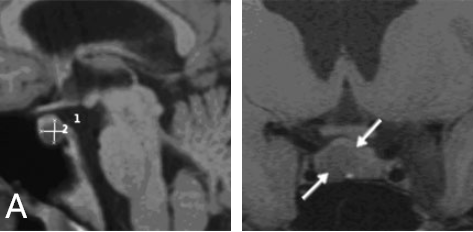

核磁共振成像显示垂体窝中有一个小肿瘤,将正常垂体向左侧移位。

INC国际神经外科医生集团旗下组织世界神经外科顾问团(WANG)成员、世界神经外科学会联合会(WFNS)内镜委员会前主席Henry W.S. Schroeder(施罗德)教授决定采用内镜经鼻手术,成功切除了肿瘤。术后一年的核磁共振成像显示,泌乳素瘤已完全切除,垂体功能正常。内分泌检查显示泌乳素水平恢复正常,其余激素的表现也十分正常,青春之花重新绽放!

术后核磁共振成像显示肿瘤已完全切除。泌乳素水平趋于正常。垂体正常工作,无需补充激素。